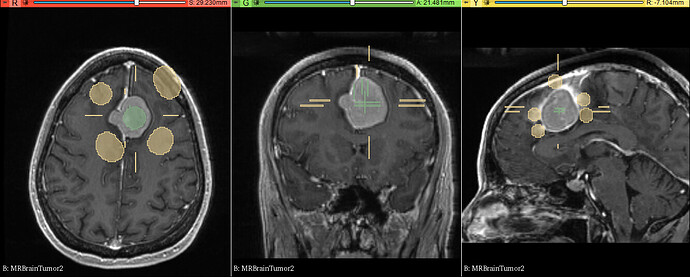

练习数据:示例数据MRBrainTumor2

• 应用笔刷或画笔涂画要分割的部分作为种子

• 换一种颜色涂画要分割组织的周围部分

• 点击预览观察分割结果是否正确

• 在错误的分割区域增加更多的种子,结果自动更新

• 点击应用得到分割结果